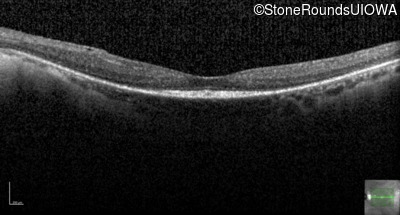

Optical Coherence Tomography - Right - 20/40 +1

Exemplar / OCT Stack

OCT Stack